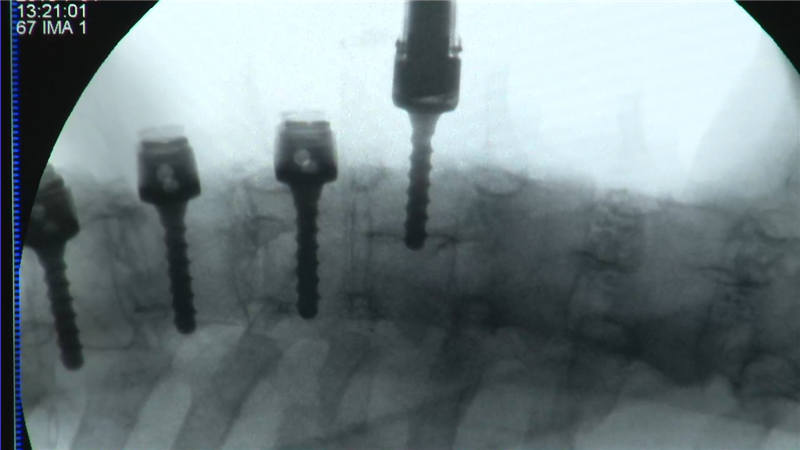

术中C臂辅助透视置钉